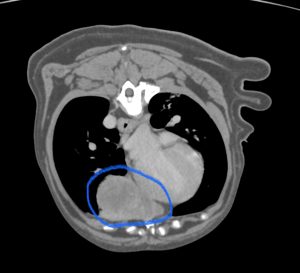

CT検査では、左前葉に7cmのしこりが1つ、右後葉に2cmのしこりが1つ見つかりました。お腹や、頭の方には腫瘍らしき病変はなく、転移性の肺腫瘍は否定的でした。左右の肺にしこりがあり、肺の中で転移している可能性が考えられましたが、その他には肺内転移を疑う病変がないため手術は可能と考えて、飼い主さんと相談の上、両方とも切除することになりました。

肺は全体の50〜60%切除すると術後に呼吸状態が悪くなるため、大きい方は肺を丸ごと切除、小さい方は特殊な器具を用いて部分切除にすることで、肺は70%ほど残せるように計画しました。